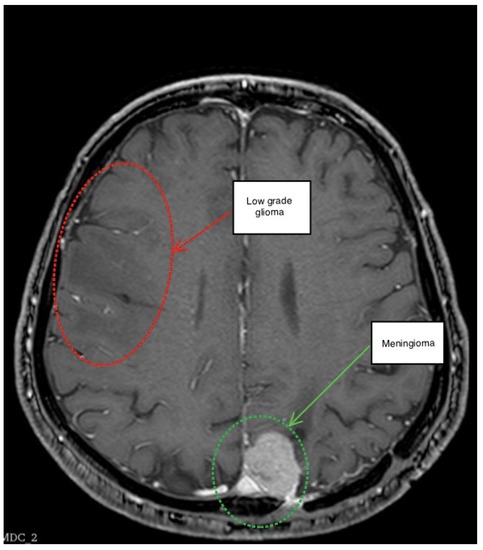

3.1. First Scenario

3.2. Second Scenario

3.3. Third Scenario